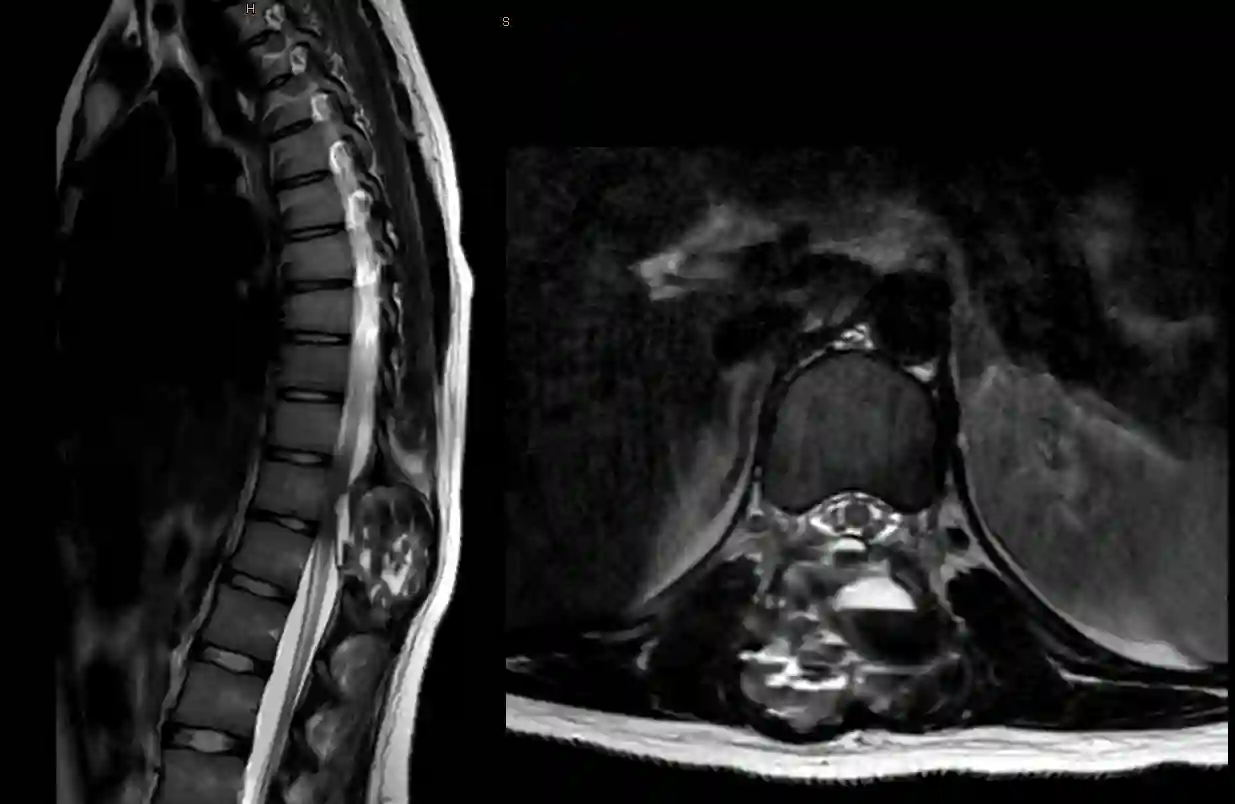

T2 MRT Sequenz eines Patienten mit einer aneurysmatischen Knochenzyste im Bereich der Brustwirbelsäule mit kompressiven Effekt auf das Rückenmark.